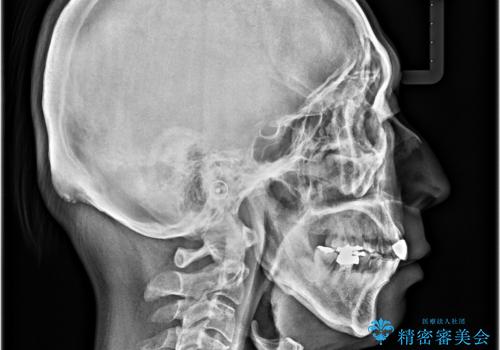

- 八重歯を気にして来院された患者様です。

上顎前歯の突出感と右上の八重歯を気にされていたので、上顎左右の第一小臼歯2本を抜歯し、ワイヤー装置にて矯正治療を行うこととしました。

食いしばりにより奥歯がすり減っており、咬み合わせが定まるまで時間がかかりましたが、整った口もに仕上がりました。